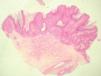

Se practicó una biopsia en sacabocados de la región axilar para estudio histopatológico. Se realizaron funciones con hematoxilina-eosina, PAS y rojo Congo (fig. 2). Se observó una papilomatosis, hiperqueratosis ortoqueratósica y acantosis epidérmica, atrofia focal del estrato granuloso y leve hiperpigmentación del estrato basal de la epidermis. En la dermis aparecía una dilatación moderada de los vasos sanguíneos superficiales. La tinción con PAS no mostró la presencia de elementos fúngicos y la tinción con rojo Congo fue negativa.

Figura 2. Tinción con hematoxilina-eoxina, x2.

El estudio histológico demuestra hiperqueratosis, papilomatosis, adelgazamiento del estrato granular y acantosis. Puede hallarse un aumento de la melanina en los melanocitos del estrato basal, una dilatación moderada de los vasos sanguíneos dérmicos superficiales y un escaso infiltrado linfocitario perivascular. Se han descrito casos de PCR sin papilomatosis3.